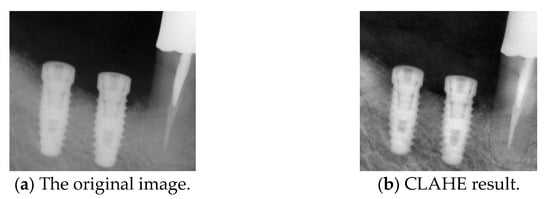

2.2.3. Contrast-Limited Adaptive Histogram Equalization